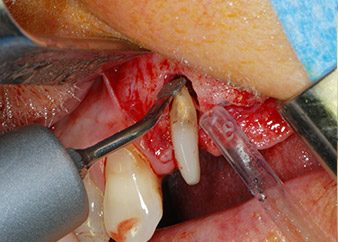

Zunächst wurde in einem Versuch, das Paro-Endo-Problem zu lösen, an der verbleibenden Wurzeloberfläche ein vorsichtiges Debridement mit einem piezochirurgischen Gerät vorgenommen (Piezomed, W&H) (Abb. 4); dann wurde der Apex mit dem gleichen Instrument im Sinne einer WSR abgetragen, um das verbleibende infizierte apikale Gewebe zu entfernen (Abb. 5). Eine retrograde Füllung war nicht notwendig, da die orthograde Füllung gerade revidiert worden war.